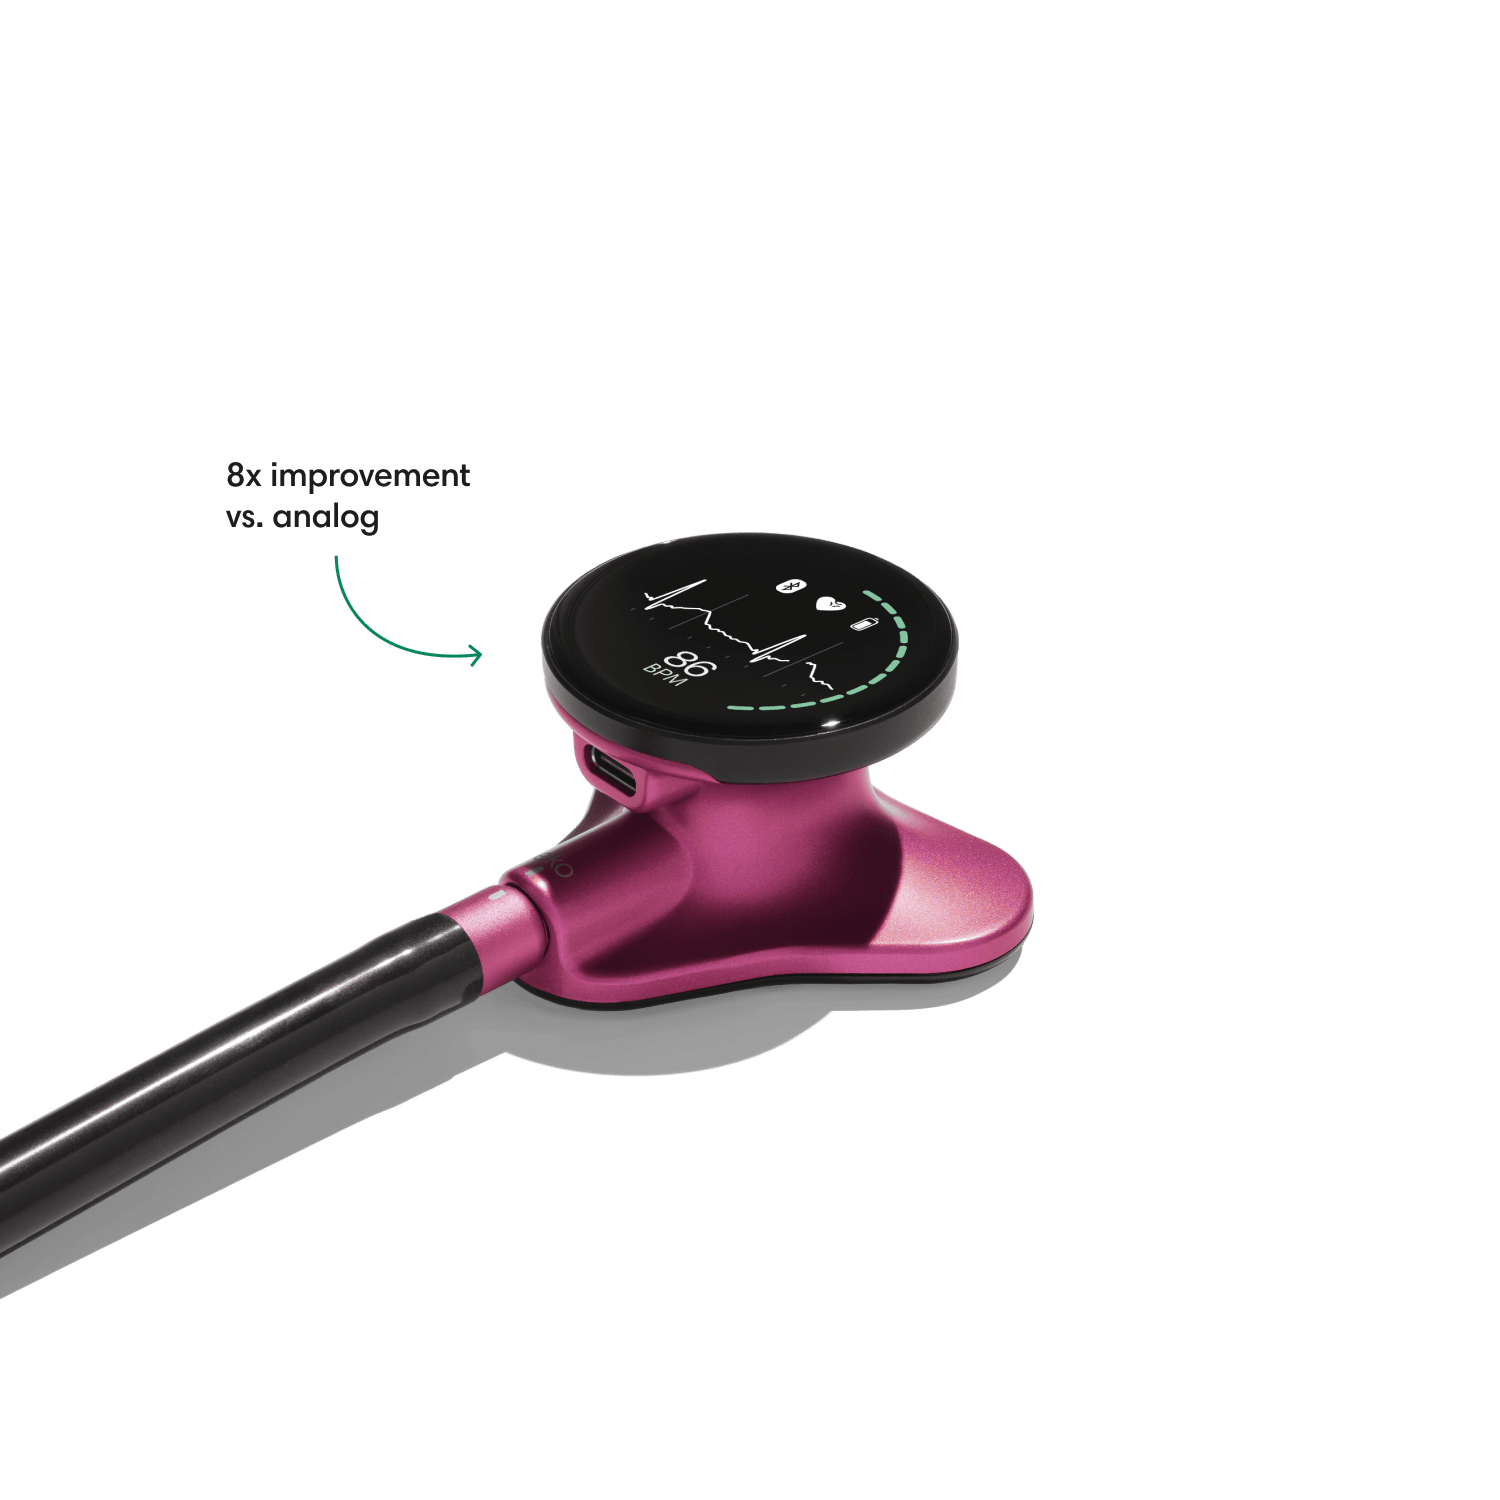

Instead of using a hollow tube like with an analog stethoscope, heart and lung sounds are delivered digitally through ear tip speakers. This results in unparalleled audio quality and sound cancellation.

- Reduces background noise 8x better vs. a typical analog stethoscope.